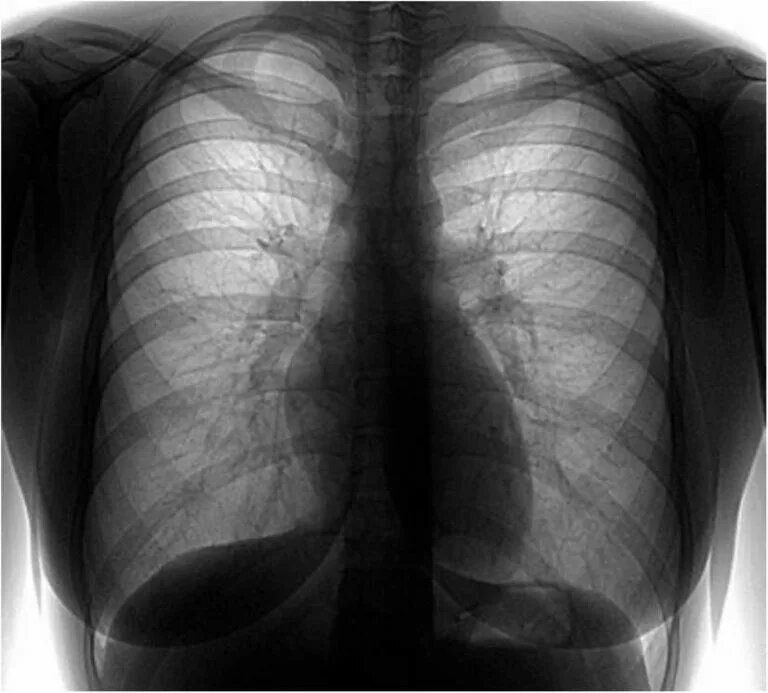

Флюорография дает общее изображение обеих легких и сердца, но с меньшей разрешающей способностью. Это помогает выявлять лишь крупные патологии.

Флюорография предлагает изображение с более низкой четкостью, что может ограничивать диагностику некоторых состояний на ранних стадиях.

2. Флюорография: Интерпретация изображений осуществляется с упрощением, направленным на быстрый анализ. При обнаружении подозрительных изменений пациент обычно направляется на более углубленное обследование, включая рентгенографию.